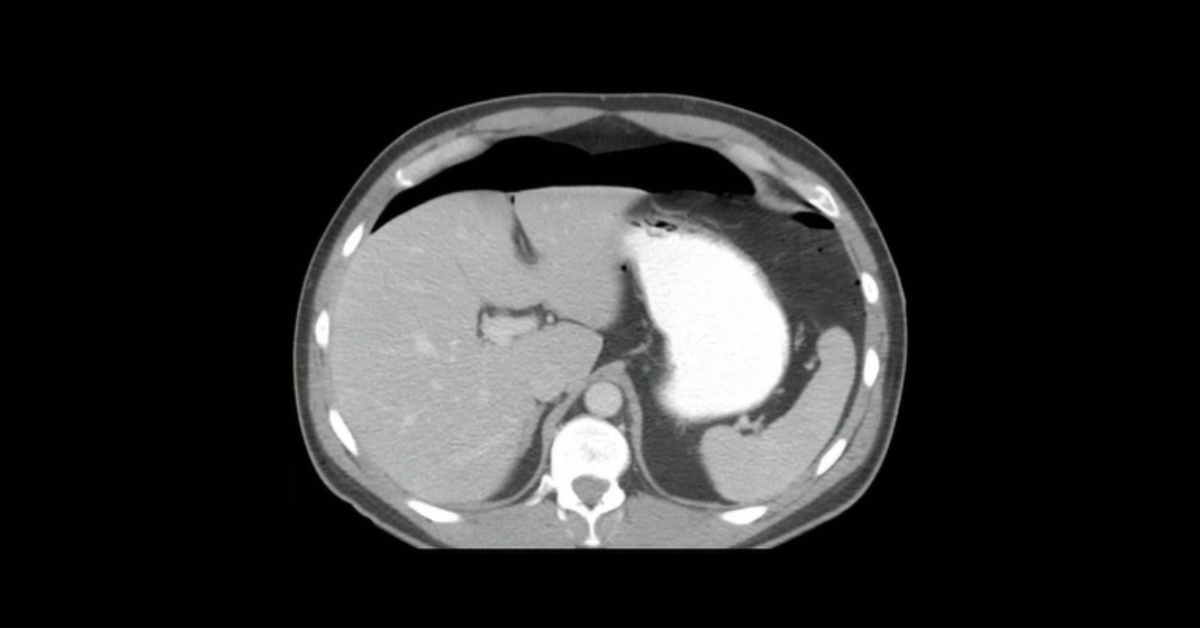

Presented by Vincent Mellnick, MD at Practical Radiology 2025. This talk will focus complications following the most common bariatric surgeries in my practice: Gastric sleeve, gastric band, and Roux-en-Y gastric bypass. The commonly encountered complications include perforation, hemorrhage, and obstruction. Knowledge of the surgical techniques and complications in both the perioperative period and long-term is crucial for radiologists.

1. Utilize CT, and as needed, fluoroscopy to identify and characterize complications of bariatric surgery

2. Understand surgical technique for gastric bypass, gastric banding, and gastric sleeve procedures

3. Help guide management by correcting characterizing post-operative bleeding, obstruction, and perforation.